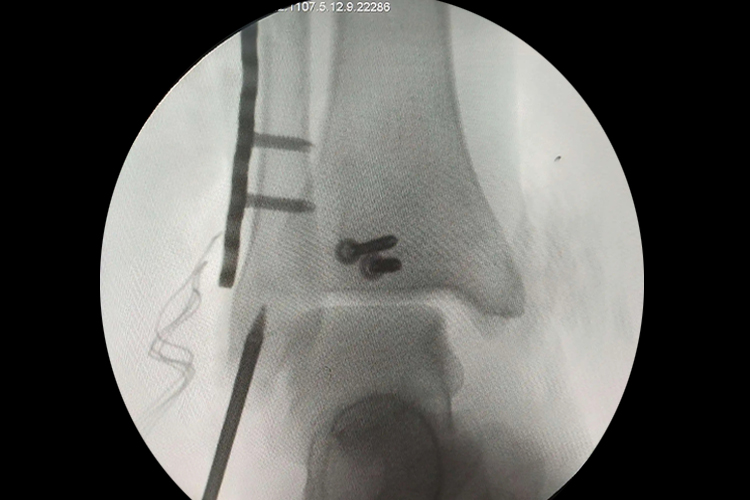

脚踝韧带手术铆钉是单皮质骨螺钉,损伤神经血管的概率很小,所以只要不侵犯周围神经血管通道,就无需反复调整螺钉的角度,避免出现螺钉松动,同时手术中也可以使用C形臂机透视辅助定位,减少了肌肉剥离范围,从而最大限度地减少了手术对踝关节结构的破坏,从而获得了更加稳定的固定效果。